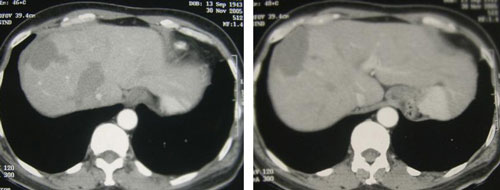

Setelah operasi, dokternya menyarankan kemoterapi yang telah disetujui Hanafi sebelumnya. Saya menghormati keputusannya. Hanafi melakukan duabelas siklus kemoterapi, bukan enam kali seperti pasien yang lain. Tumor pada livernya tidak ada perubahan. Kemoterapi ditinggalkan dan ia menjalani dua terapi RFA (radiofrequency ablation). Prosedur ini pun gagal.

Pilihan berikutnya adalah dengan kemoterapi lagi atau operasi liver. Ia menolak keduanya! Ia belajar dari pengalamannya. Sekarang biar ia menceritakan pada anda pengalamannya …